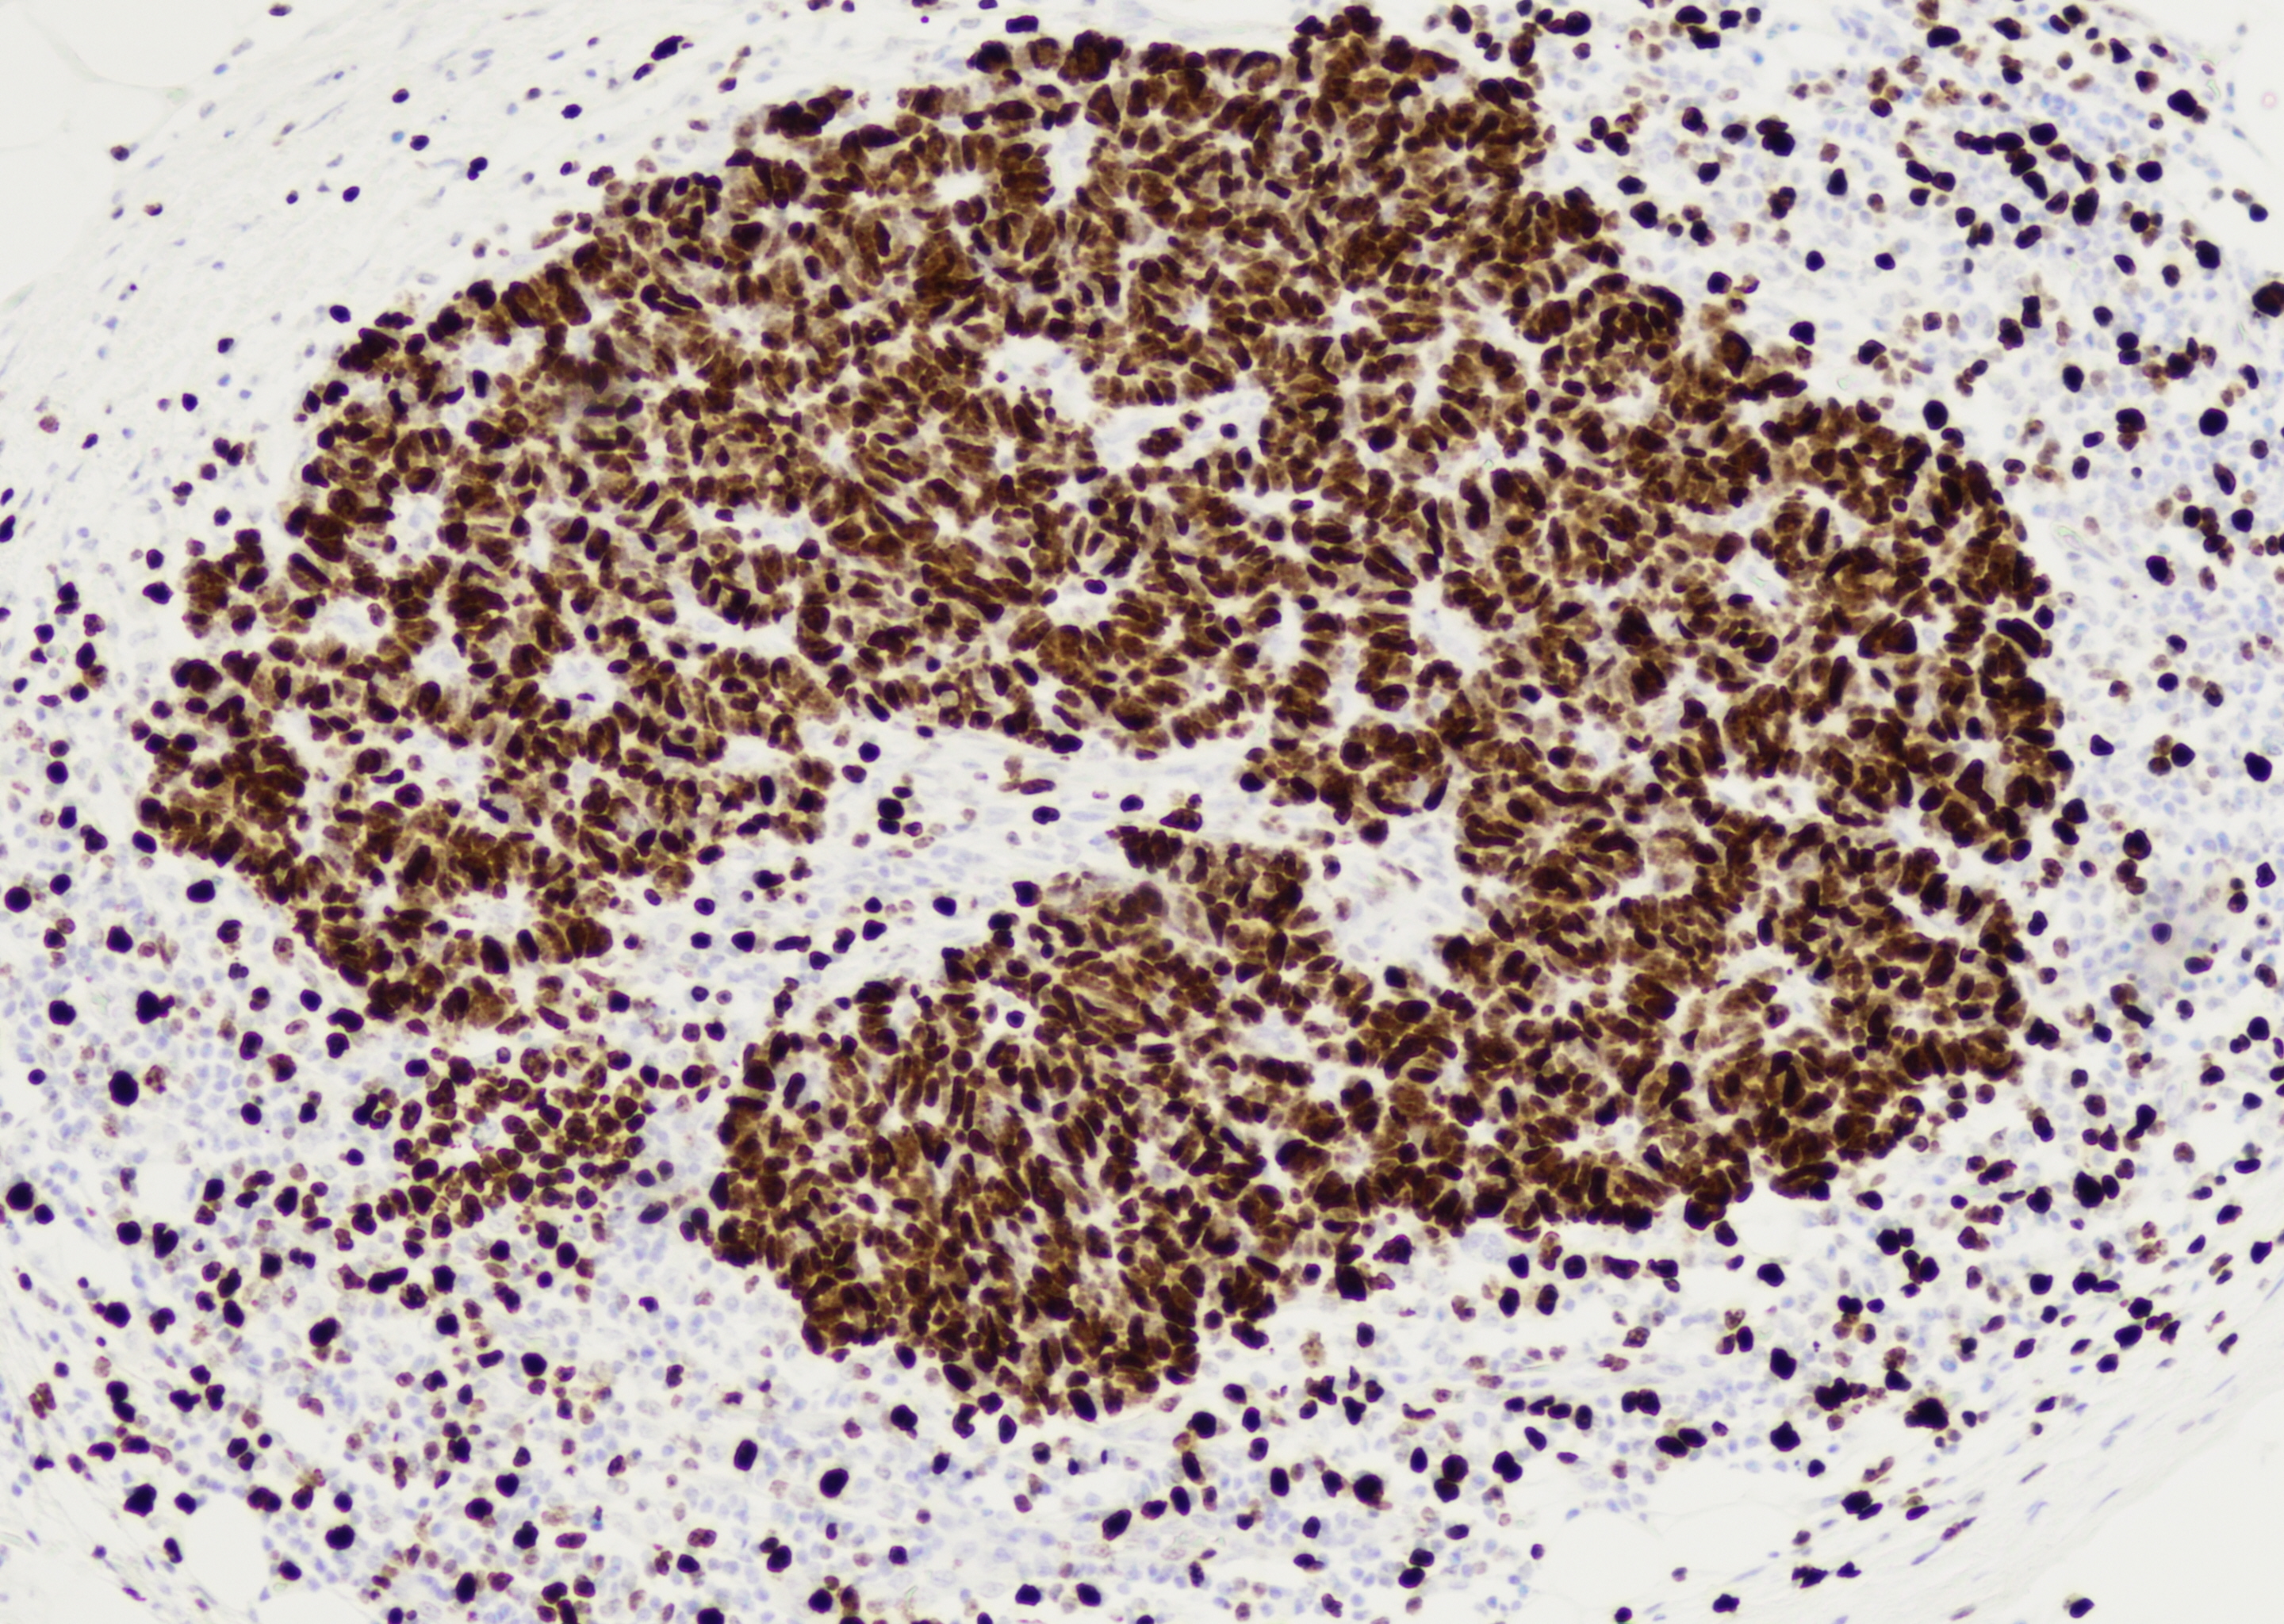

Ki-67: 99%